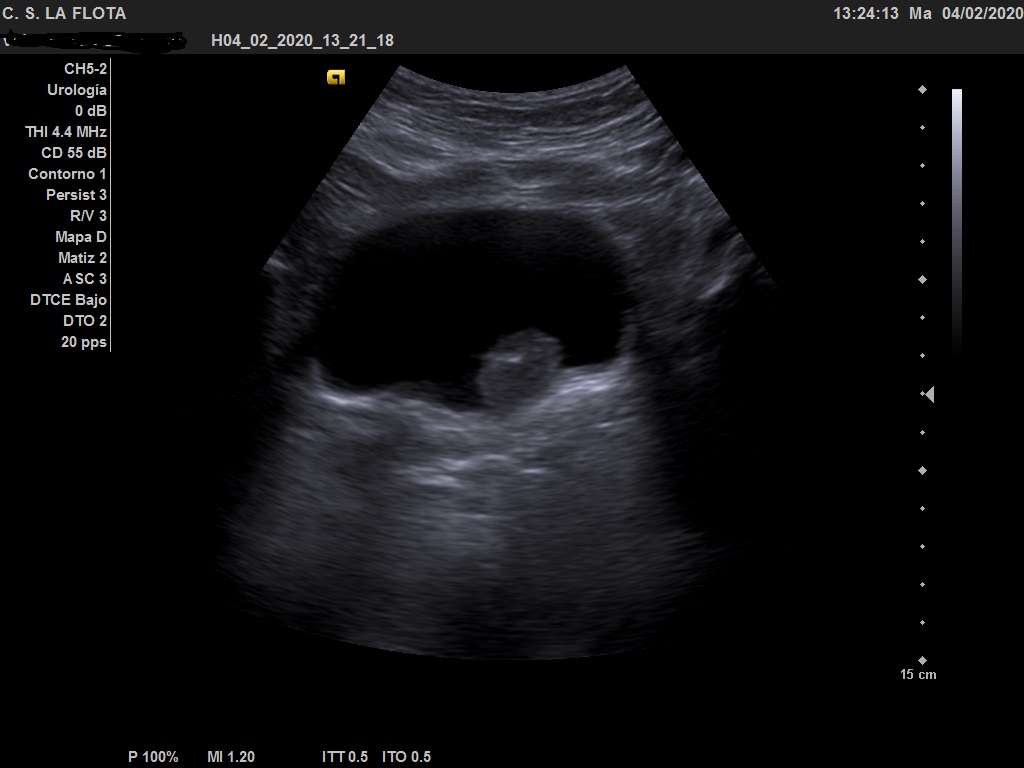

Ecografía clínica: riñones de tamaño y morfología normal, con buena diferenciación corticomedular y sin dilatacion de vias. En vejiga lesión polipoidea  de 25*18 mml.

Ante los hallazgos ecográficos se derivó al paciente a urología con copia de las imágenes. En urología solicitan cistoscopia sin precisar más pruebas de imagen.